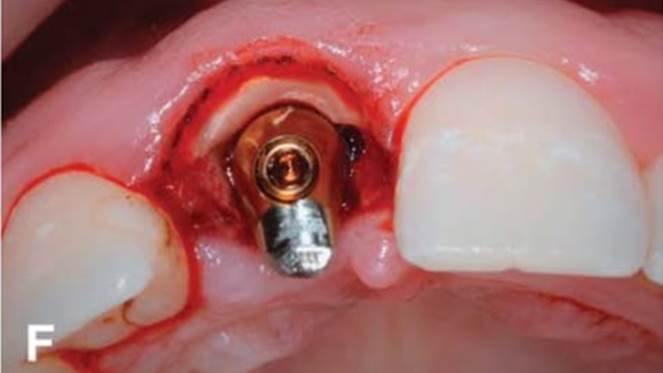

Clinical case: Replacement of fractured central incisor (#11) with immediate implant

& Root Membrane Technique

- Courtesy of Dr. Miltiadis Mitsias, Greece -

AnyRidge, Root Membrane Technique, retrospective study, long-term study, immediate implants, bone resorption, bone preservation, Dr. Miltiadis Mitsias,survival, success, maxillary anterior, single replacement

AnyRidge implant system, Root Membrane kit

The Root Membrane Technique: A retrospective clinical study with up to 10 years of follow-up./Implant Dent. 2018 Oct;27(5):564-574

https://www.ncbi.nlm.nih.gov/pubmed/30161062